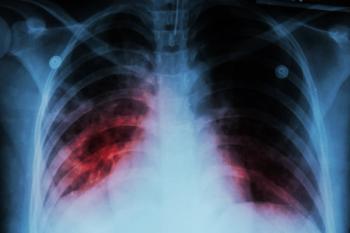

In 2022 alone, an estimated 10.6 million new TB cases were reported, mainly in low-income regions, highlighting the urgent need for further efforts in TB prevention and control.